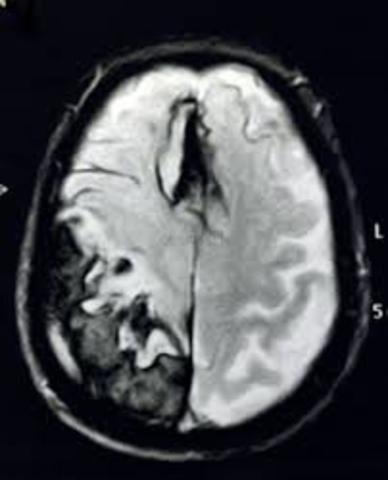

TAC cráneo, imágenes lacunares bilaterales gangliobasales. No se objetiva lesión hemorrágica o isquémica configurada. En esta fecha se le realiza el respectivo exámen del TAC, ya que este exámen se necesito de una preparacion previa para poder realizarlo.

• 13.DIAGNOSTICO (DX)

13.DIAGNOSTICO (DX)

Después de un proceso minucioso y al ver los resultados de los respectivos exámenes que se le realizaron al paciente previamente en los meses anteriores. Llegamos a la conclusión de que elpaciente presenta una obvia lesión en la tercera circunvolución frontal, en el área 44 de Brodman. Por ello como diagnóstico después de todos los respectivos exámenes realizados el paciente posee una Afasia de tipo Broca. Con la cual hemos elaborado un tratamiento de acuerdo a sus necesidades.